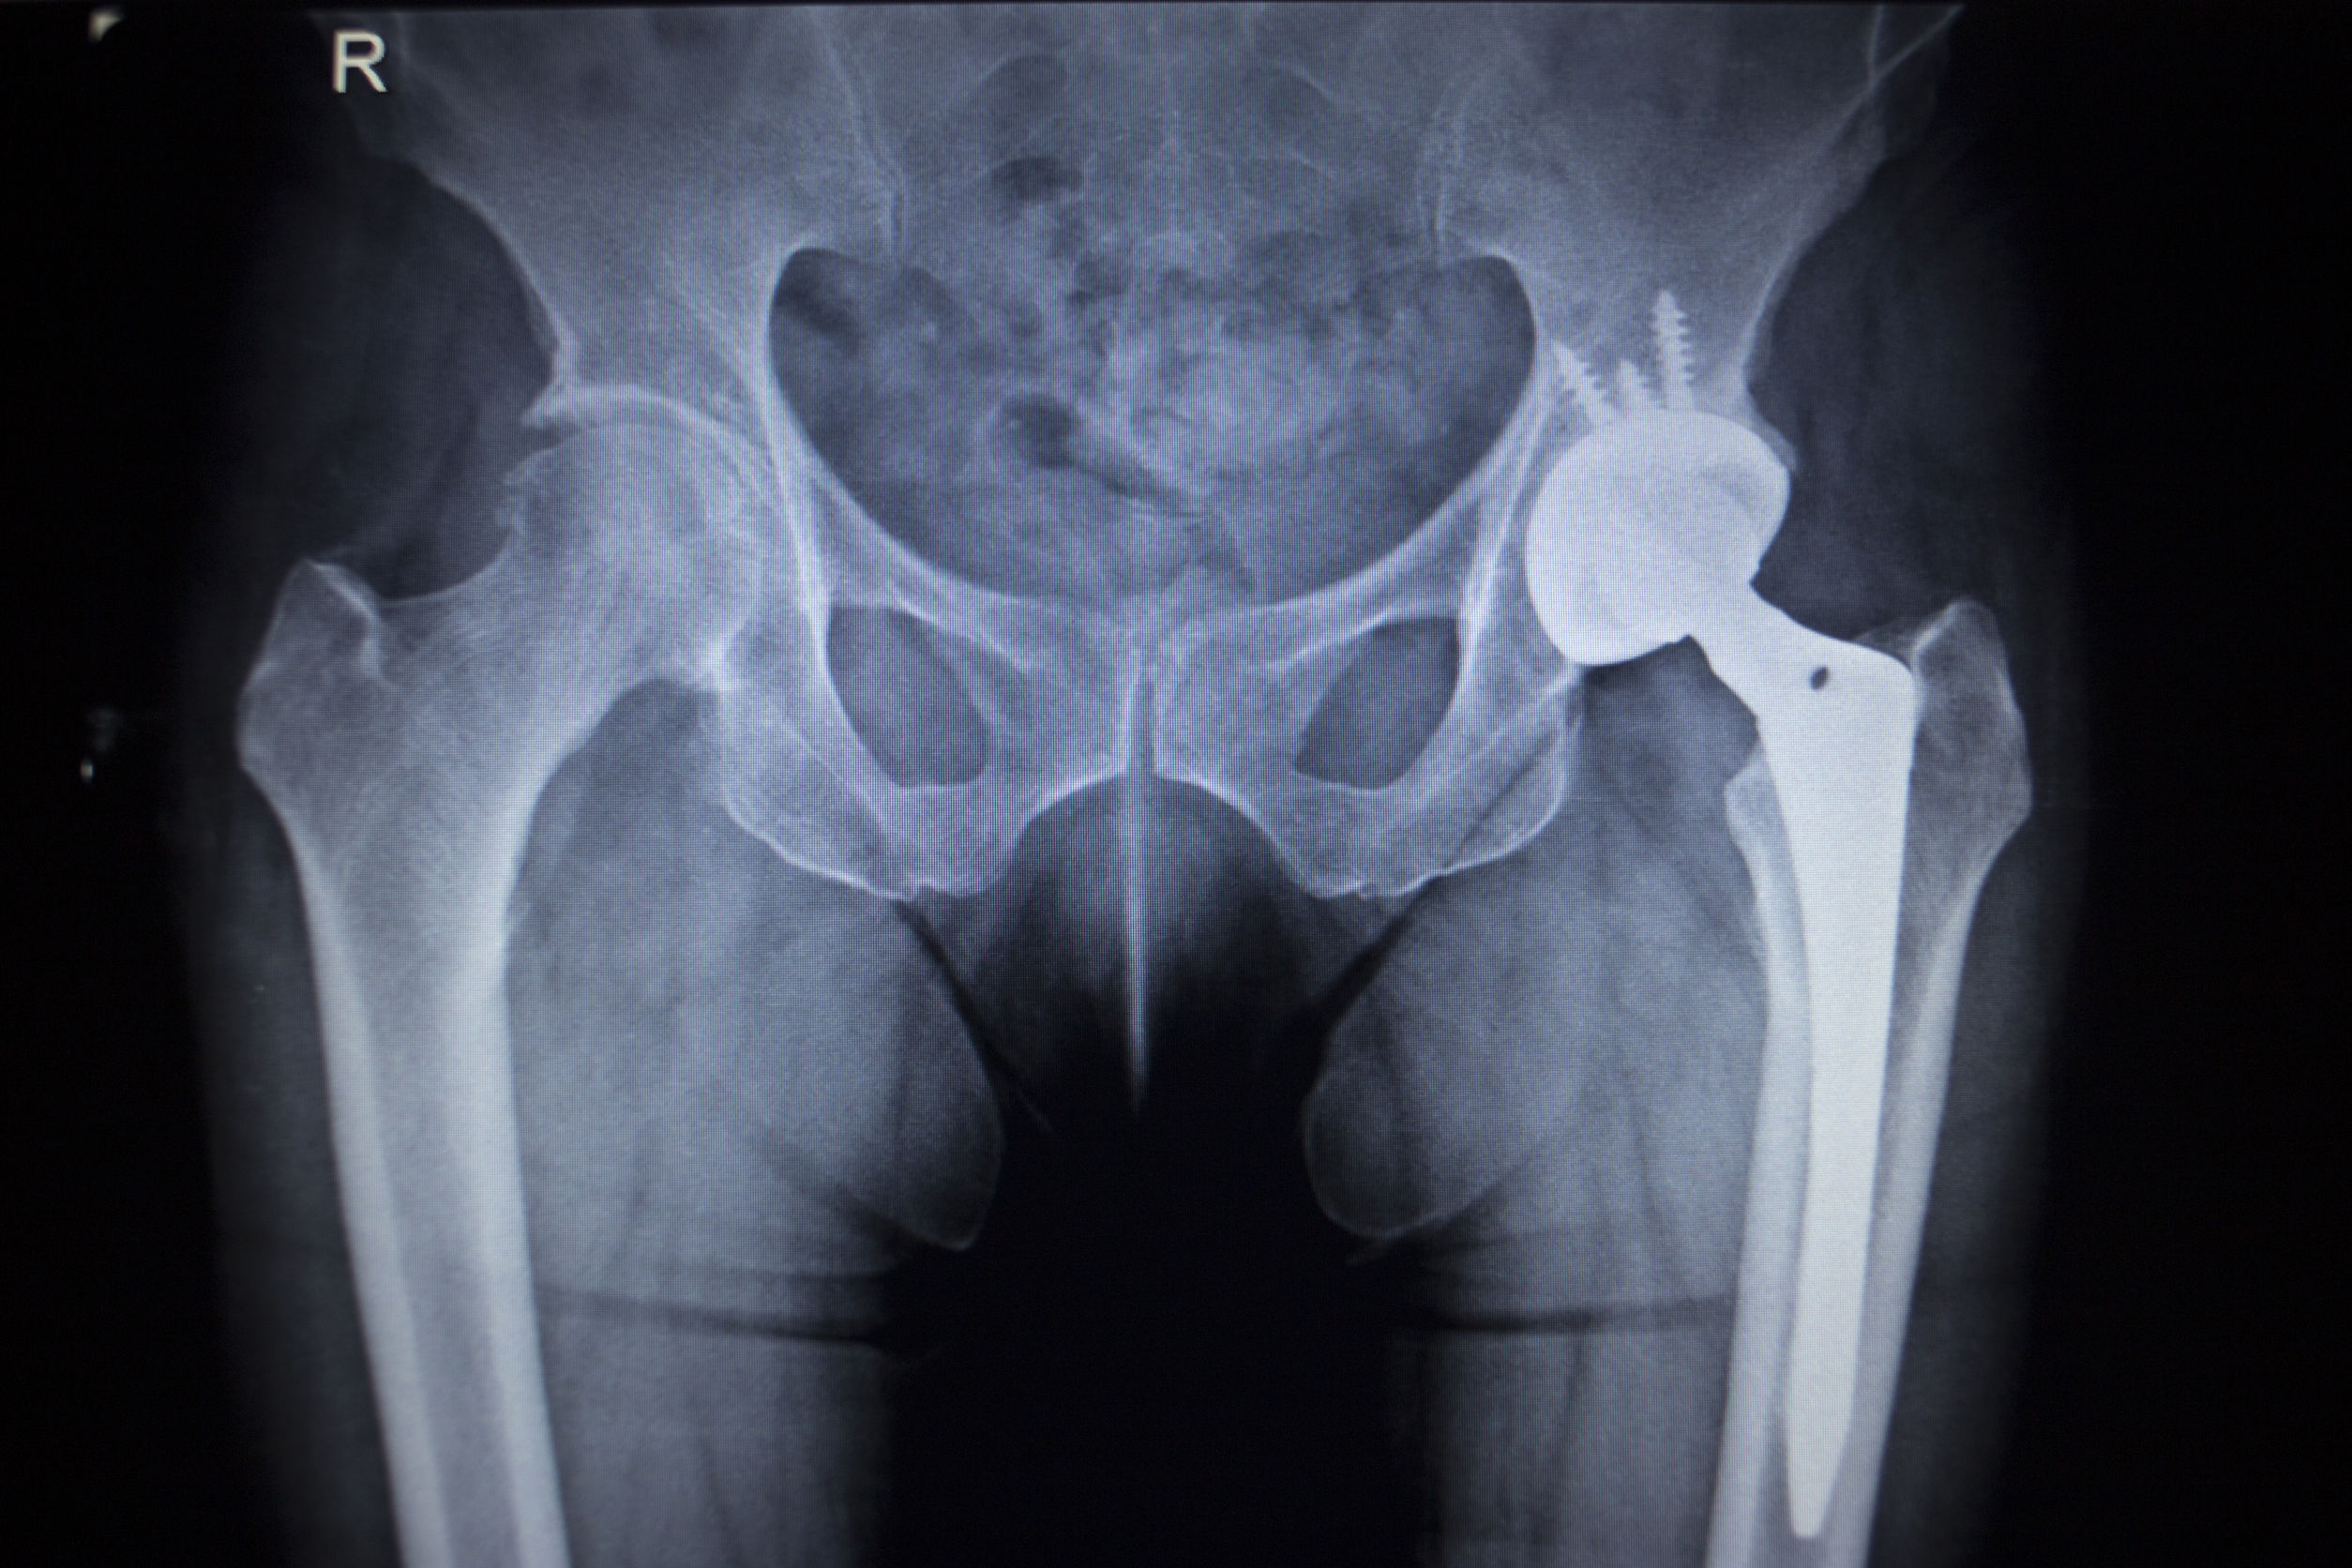

Hip Replacement Procedure, Symptoms, Types of Implants and Risks J&J Hip Implant Case the delhi high court on thursday directed johnson and johnson to make interim payment of ₹ 25 lakh each. 11 jan 2019 7:31 am gmt. The national consumer disputes redressal. The delhi high court had. the delhi high court on may 30, 2019, directed american multinational johnson and johnson (j&j) to pay rs 25 lakh each to.. J&J Hip Implant Case.

Revision Total Hip Replacement OrthoInfo AAOS J&J Hip Implant Case the delhi high court on may 30, 2019, directed american multinational johnson and johnson (j&j) to pay rs 25 lakh each to. j&j faulty hip implant case: The mumbai police are likely to file a formal case against johnson & johnson over a complaint that. the supreme court (sc) on friday disposed of a public interest litigation. J&J Hip Implant Case.